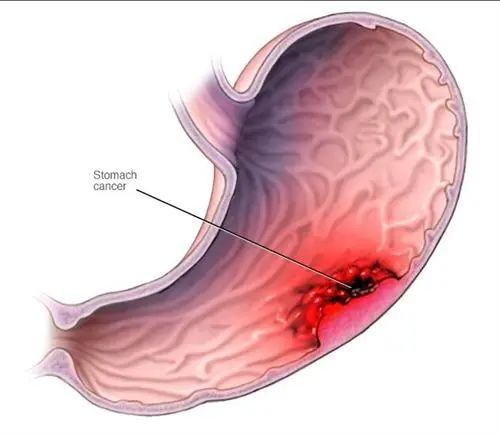

胃癌对人体的影响

胃癌属于恶性肿瘤,且恶性程度较高。疾病分期越晚,预后相对越差。如早期发现胃癌,早期诊断、早期手术,危害相对减少。中晚期,尤其晚期患者,即使进行手术治疗,其生存率、生活质量都会受到严重影响。